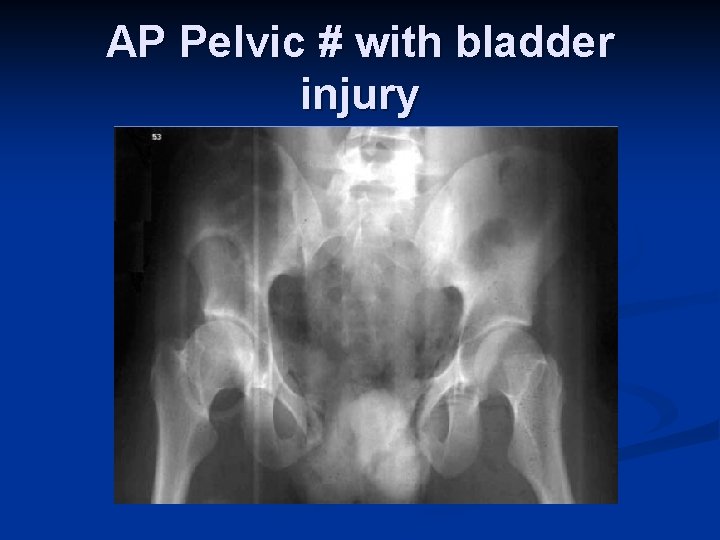

AP Pelvic # with bladder injury